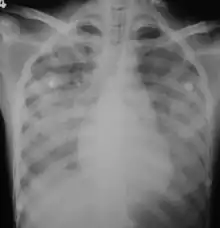

Imaging

In those who have lung involvement, a chest X-ray may demonstrate diffuse alveolar opacities.[21]